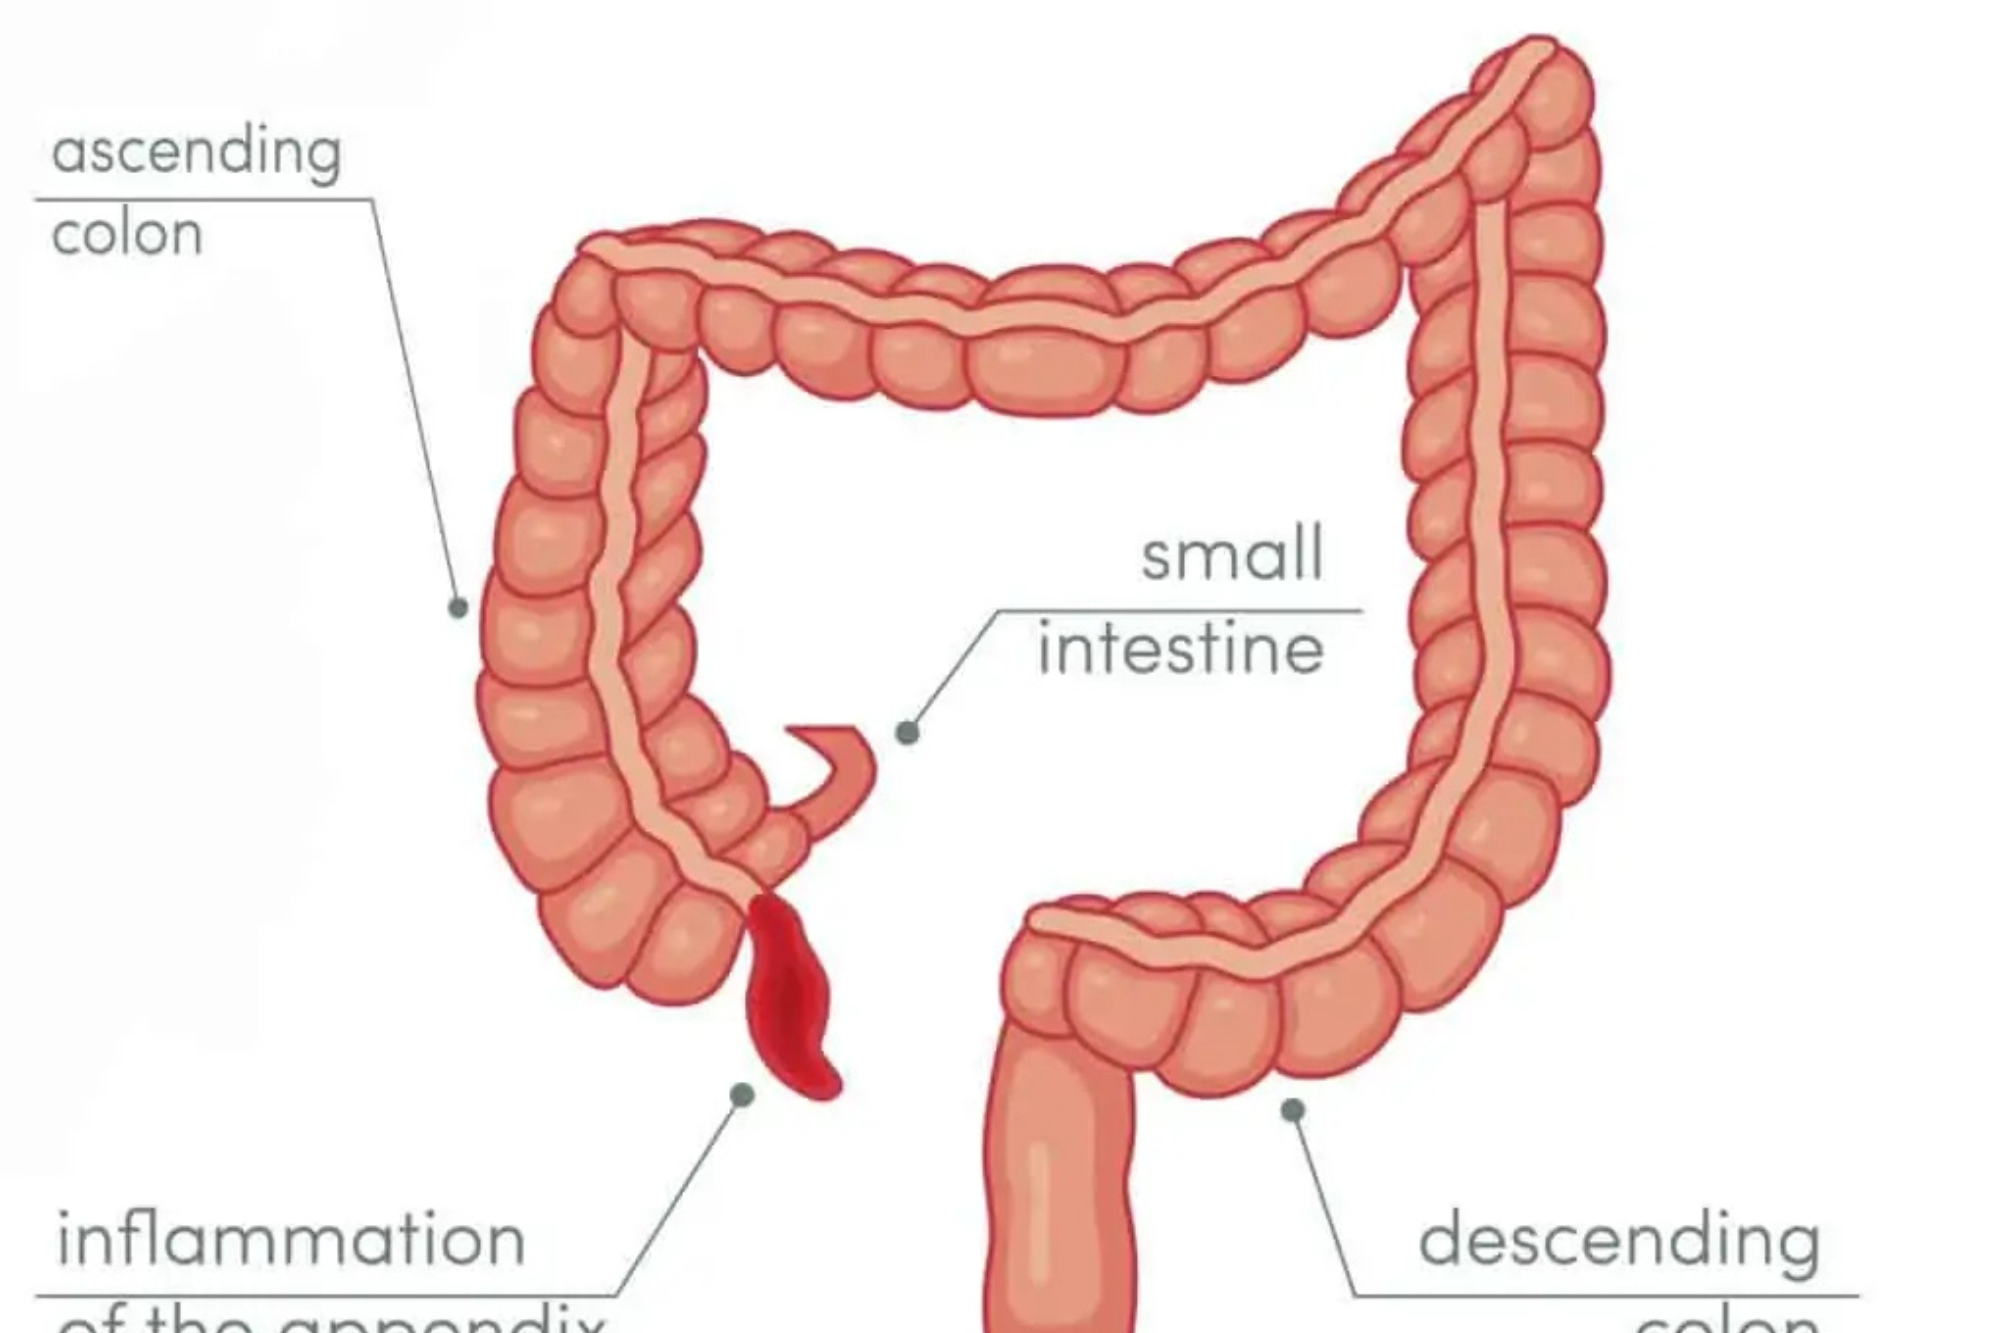

Appendicitus

Appendicitis is a medical emergency where the appendix becomes inflamed and filled with pus.